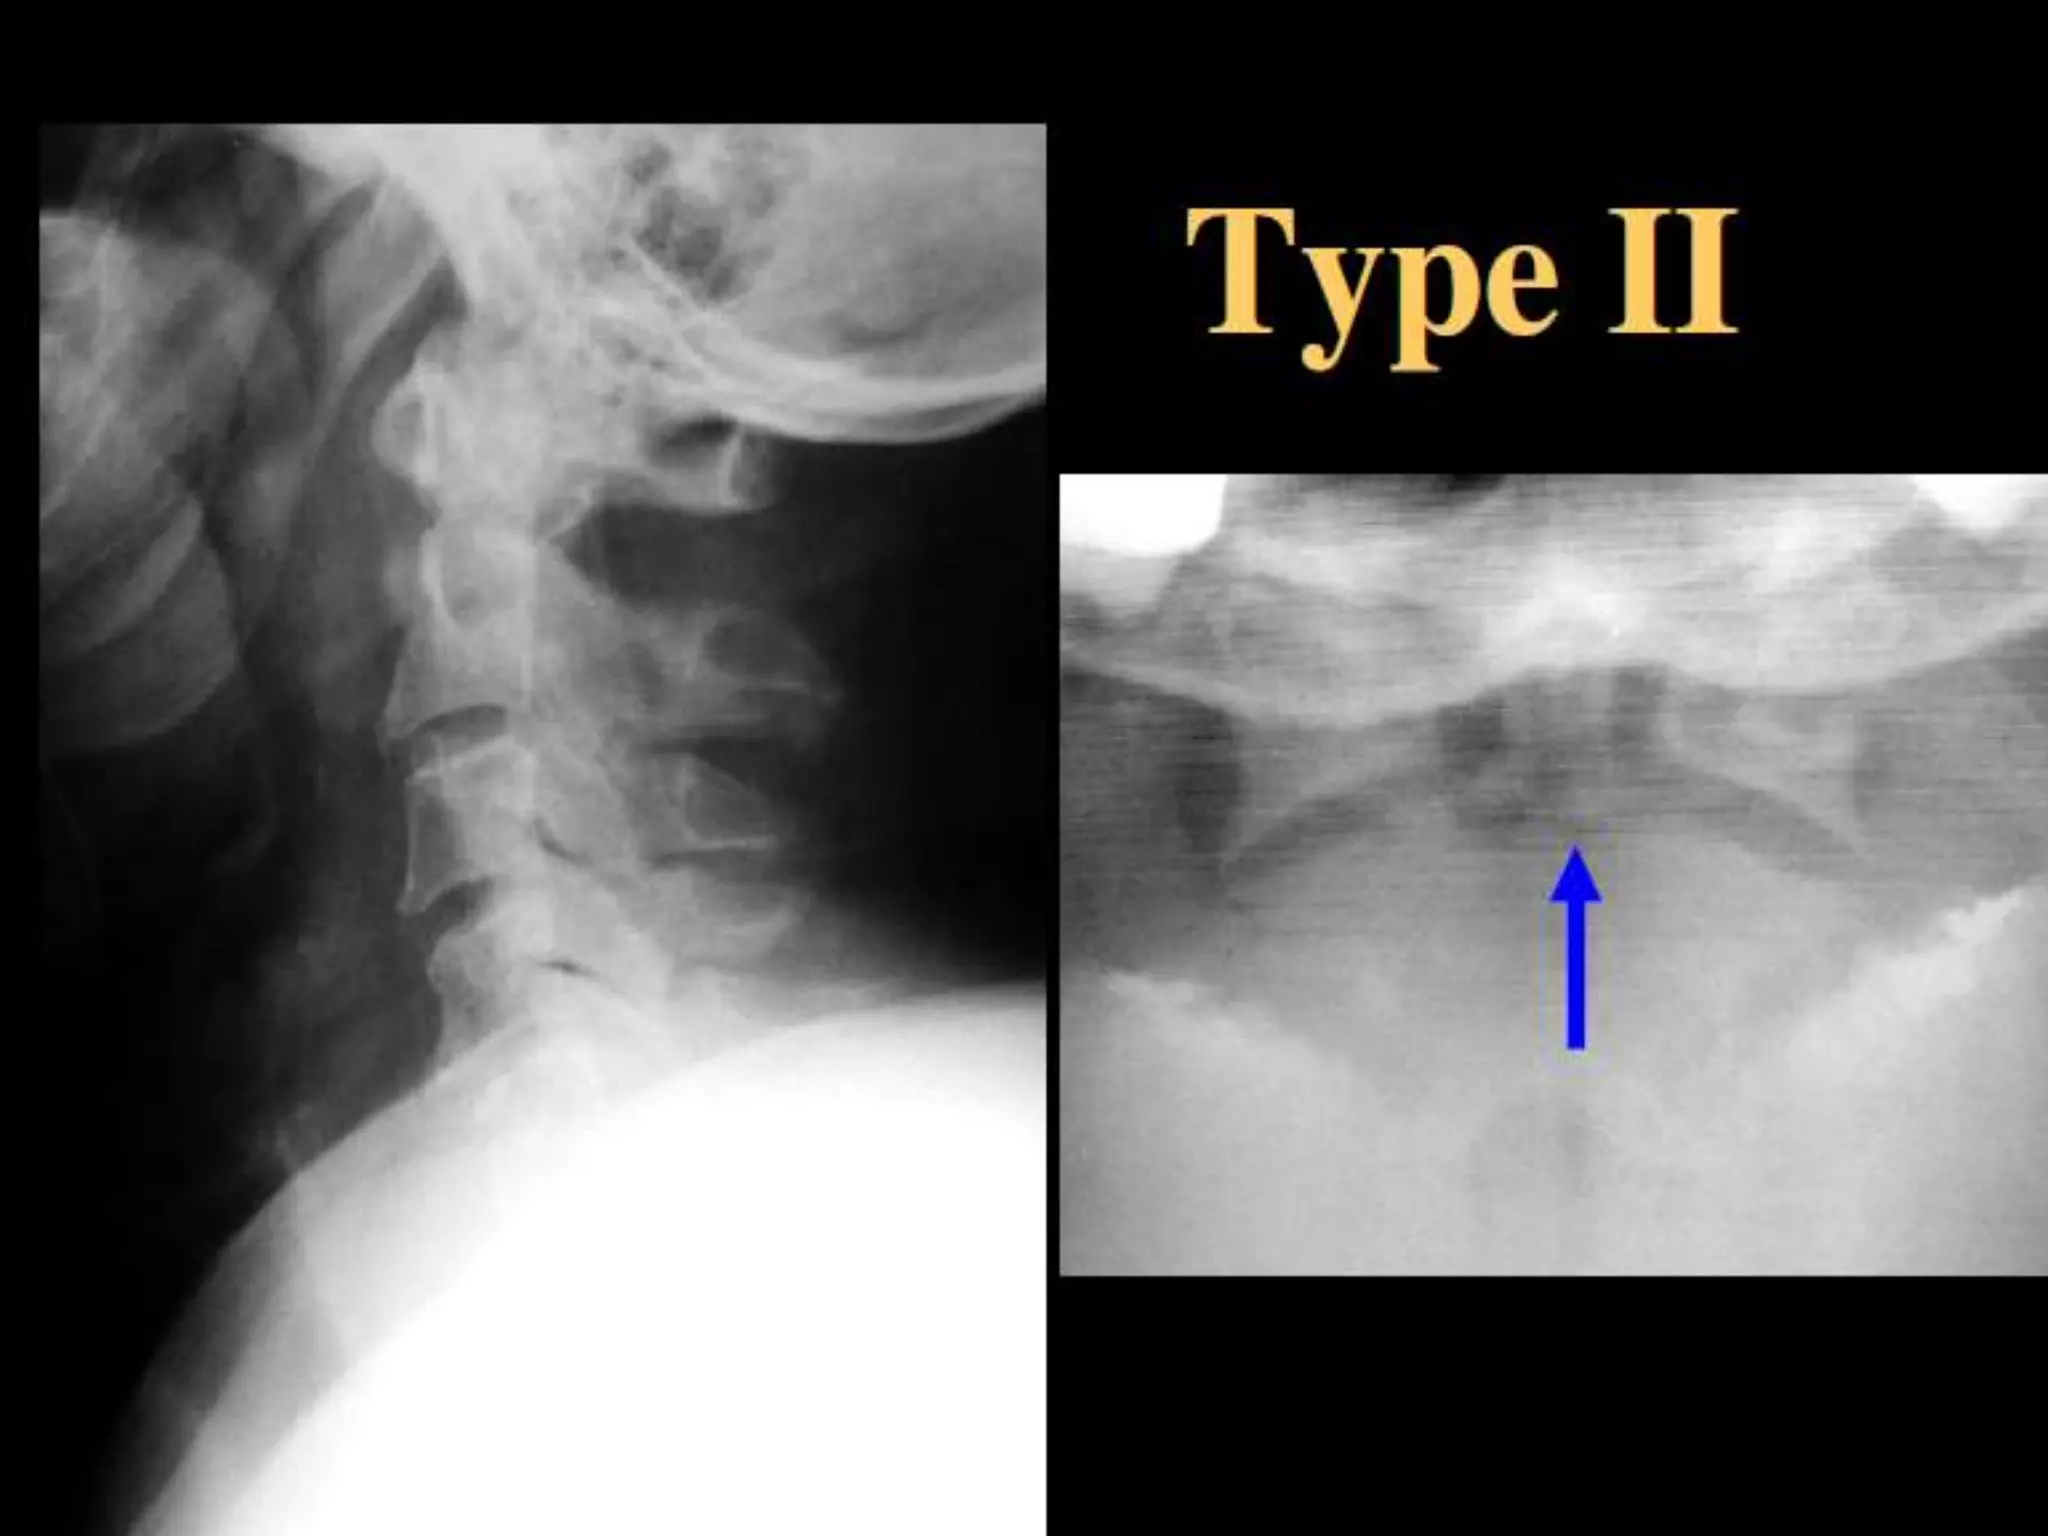

Odontoid (Dens) Fractures:

• 11-13% c-spine injuries (up to 27% in some

series).

– 75% of cases are children.

• Classification

– Anderson & D’Alonzo (I, II and III).

• Associations

– atlantoaxial dislocations.

– Jefferson FX.

• Radiography may be subtle.

• Prevertebral STS nasopharynx.